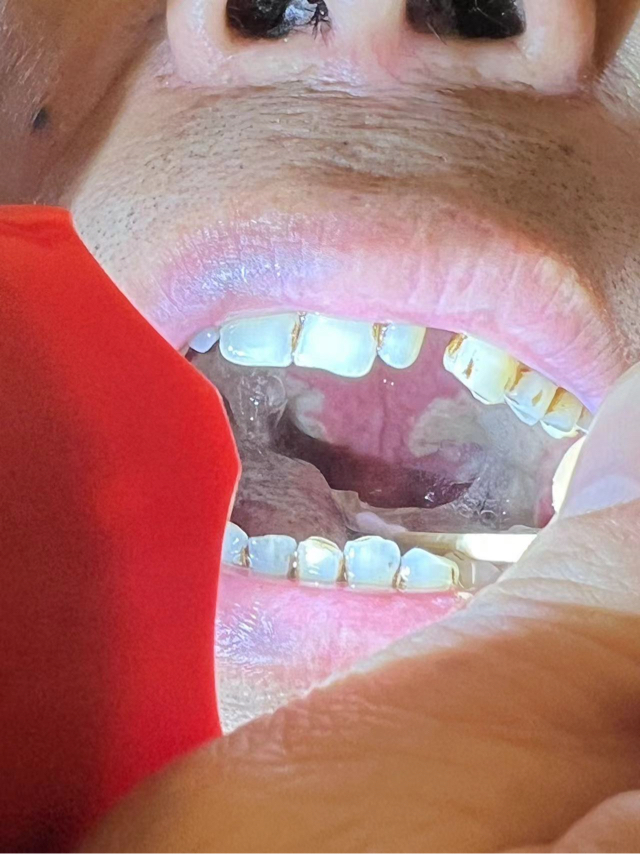

外周T细胞淋巴瘤!非常非常严重的口腔溃疡,怎么办!

现在应该比这个还严重!!!真的不知道怎么办,饭也吃不了,水也喝不了!